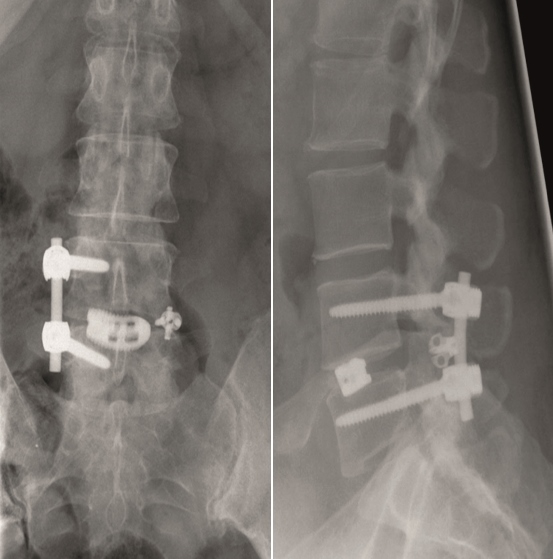

Case 4 : ALIF L4-L5 non union

A 40-year-old man 5 years after ALIF L4-L5 using SynFix with axial low back pain. The CT scan shows locked pseudarthrosis (Fig 17). Nonoperative treatment failed. The treatment option was bilateral Facet Wedge at L4-L5.

A less invasive approach was used with Insight Retractor using the bilateral Facet Wedge. No bone graft. X-ray follow-up after 3 months and CT assessment after 6 months (Fig 18-19).